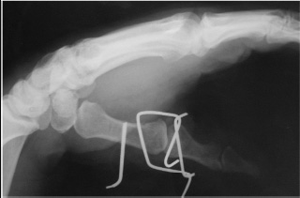

Рис. 2. Фиксация перепомовывиха 1-ой пястной кости системой Эйджи. а. переломовывих 1-ой пястной кости б. и в. фиксация перелома и вправление вывиха системой

кости, у 8-и больных (34.78%) 1-ой, у 3 больных (13.05%) 2-ой пястной кости. У 19 больных (82.6%) наблюдались повреждения правой кисти. Объективное обследование проводилась по общепринятым методикам. Для диагностики характера повреждения костных структур пациентам выполнялась рентгенография травмированной кисти в двух стандартных проекциях. Всем была сделана операция с использованием экстензионной системы Эйджи (рис.2).

Материал и методы. Изучены результаты лечения в НЦТО за 2008-2012 годы 23 больных с переломами головок пястных костей. Возраст пациентов на момент получения травмы колебался от 19 до 45 лет. Среди этих пострадавших значительно преобладали мужчины (18человек 78.26%); подобные травмы у женщин возникали примерно в четыре раза реже (5человек 21.74%). У 12 больных (52.17%) были переломы головки 5-ой пястной